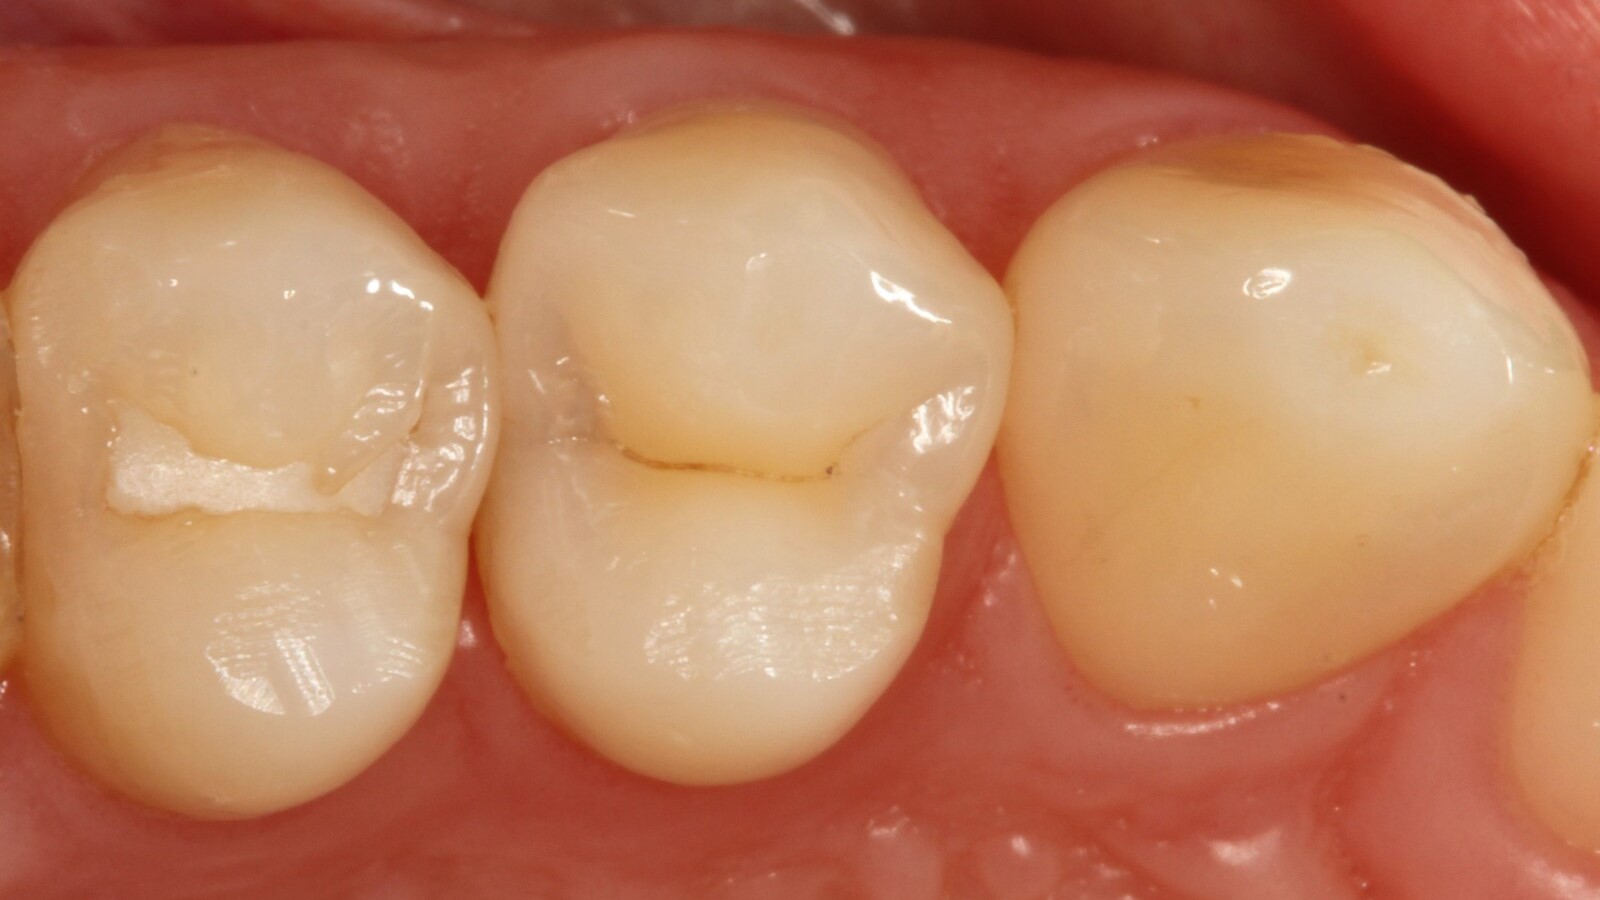

Prof. Dr. Claus-Peter Ernst, Zahnarzt und Lehrbeauftragter an der Universitätsklinik der Johannes Gutenberg-Universität in Mainz, verwendete Venus Bulk Flow ONE zur Restauration der Aproximalkaries eines Patienten an der distalen Fläche des ersten oberen linken Prämolaren. Dieser Fall veranschaulicht die Vielseitigkeit und einfache Anwendung von Venus Bulk Flow ONE, die es zu einer ausgezeichneten Wahl für eine Reihe von Indikationen macht, während es gleichzeitig eine außergewöhnliche Festigkeit und Ästhetik bietet.

Professor Ernst identifizierte zunächst die versteckte Karies und öffnete die kariöse Läsion, um dem Patienten das Problem zu veranschaulichen (Abb. 1-2). Anschließend exkavierte er die Karies, präparierte die Kavität und setzte eine Teilmatrize ein (Abb. 3), bevor er die Kavität mit Adhäsiv versiegelte (Abb. 4). In einem einzigen Schritt füllte er die Kavität mit Venus Bulk Flow ONE (Abb. 5). Nach der Fertigstellung polierte Prof. Ernst die Restauration (Abb. 6) und fertigte ein Kontrollröntgenbild an, das ebenfalls die hervorragende Röntgenopazität von Venus Bulk Flow ONE zeigt (Abb. 7).